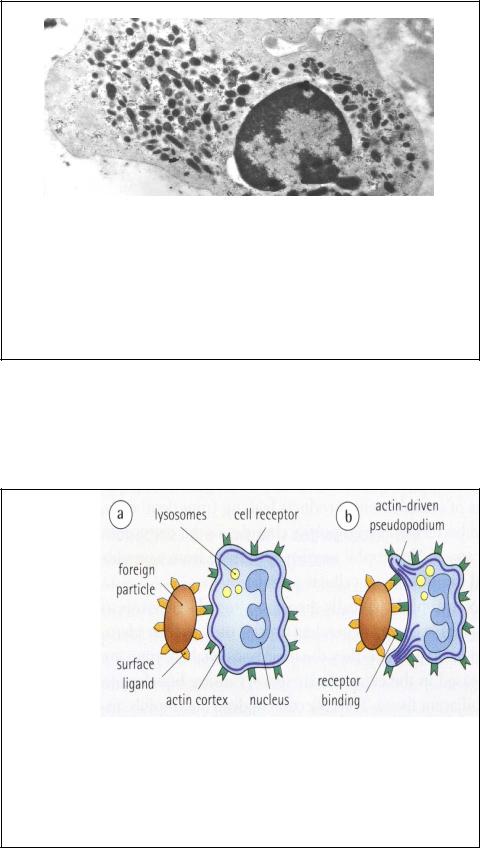

Нейтрофилы, имеющие рецепторы хемоаттрактантов (N-формил-метионил- пептидов), мигрируют в область тканевого повреждения, где они реализуют свою защитную функцию. При этом многие хемоаттрактанты являются и активаторами (метаболиты арахидоновой кислоты). Нейтрофилы способны фагоцитировать чужеродные частицы (бактерии, мертвые клетки и др.). Фагоцитоз начинается с распознавания антигена через рецепторы к опсонинам (Fc-фрагментам антител и белков комплемента, связавшихся с бактериями или их фрагментами). Цитоплазма нейтрофила содержит также различные антиоксиданты для разрушения потенциально токсичных перекисей, которые генерируются во время лизосомальной активности69 . Ps –

псевдоподии, N-ядро, g- гранулы.

ФАГО- |

псевдоподии |

ЦИТОЗ У |

НЕЙТРО- |

ФИЛОВ |

поверх- |

ностные |

связывание |

актиновая |

ядро |

рецепторов |

кора |

a)Нейтрофилы имеют мембранные рецепторы (к опсонинам - Fcфрагменту иммуноглобулинов и фракциям комплемента, связывающимся с чужеродными белками и бактериальным полисахаридами). Нейтрофилы не фагоцитируют материал, с которым у них нет специфического связывания.

b)Первый шаг на пути фагоцитоза – связывание чужеродной частицы со

специфическим рецептором. Клетки образуют псевдоподии, чтобы

70

окружить частицу – для этого производится сборка и диссимиляция актиновых филаментов.

c)Псевдоподии сливаются, полностью окражая частицу и образуя эндоцитозный пузырек. В окончательном «склеивании» мембран принимают участия специфические белки.

d)Поглощенная частица оказывается внутри фагосомы.